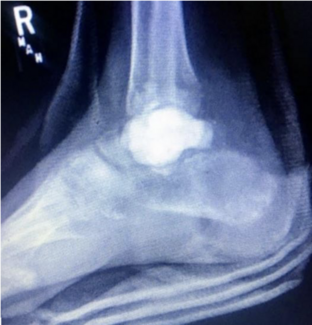

In this case report the authors discuss the surgical technique and outcome for a single tibio-calcaneal arthrodesis with the combined use of a femoral head allograft with a proximal humerus locking plate. In the case highlighted, the authors...